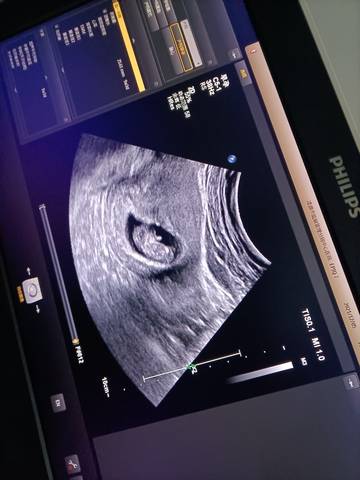

哪位亲帮我看看男宝女宝谢谢谢谢

其实通过这些是看不出来的,而且也不准确,在怀孕期间不要想太多,我觉得只要宝宝发育好的话就可以。